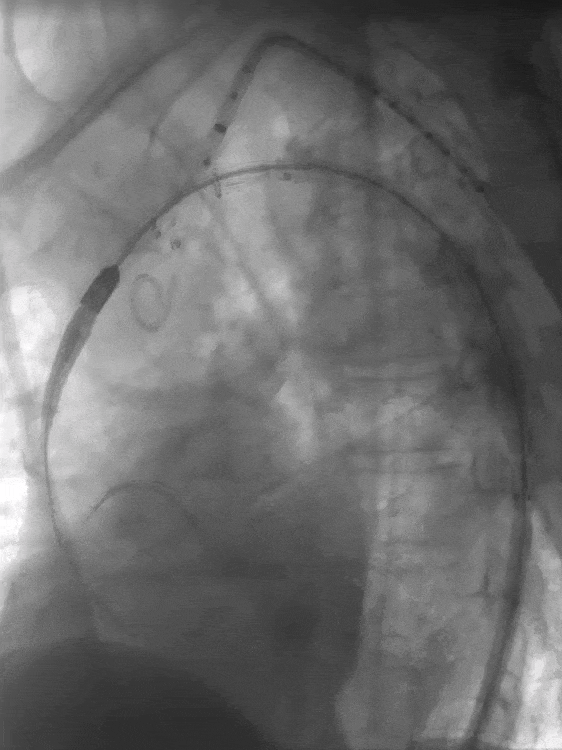

5. 左锁骨下动脉造影示:左锁骨下动脉少量造影剂外漏,根据术前计划,置入12-58mm LifeStream球扩覆膜支架,短肩球囊设计,避免导丝缠绕,顺利通过病变,并扩张释放。

导入LifeStream支架

球扩LifeStream支架

6. 最后造影效果满意,胸主动脉支架位置良好,血流通畅,无明显内漏,弓上三分支血供良好,左锁骨下动脉正向血流、双侧颈动脉和椎动脉显影好,颅内动脉显影好。

LAO术后造影

RAO术后造影